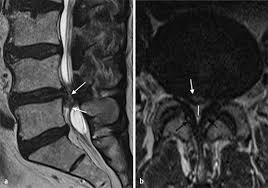

Bandscheibenprotrusion l4/5. They are relatively easy to overlook as they do not impinge upon the spinal canal. Die Bandscheibenprotrusion der LWS beschreibt nun den Zustand in dem sich einer der Kerne einer Bandscheibe nach hinten vorgewölbt hat und auf Teile des Rückenmarks oder zentrale Nerven drückt. Die Symptome ähneln dann denen eines Bandscheibenvorfalls.

They do not narrow the subarticular recess but compresses the exiting nerve root only thus clinically mimicking a posterolateral disc from the level aboveAs posterolateral discs are common as is multilevel. Computertomographisch zeigten sich ein Vakuumphänomen und eine Bandscheibenprotrusion mit Forameneinengung rechts L45 bei. Die Bandscheibenprotrusion auch Bandscheibenvorwölbung oder inkompletter Bandscheibenprolaps ist eine mit dem Alter zunehmend häufiger zu beobachtende Veränderung im Bereich der Wirbelsäule.

These levels were investigated in this study as degeneration occurs most often and earliest in these three lower vertebral levels 17 fourth and fifth lumbar spine vertebrae and the first sacral vertebra were evaluated for disc bulging and protrusion See Lumbar Artificial Disc Replacement for Chronic Back Pain A high intensity zone HIZ is seen at L4-L5 Depending on the extensiveness. Es wurde eine ausgeprägte Osteochondrose mit Pseudolisthese und Bandscheibenprotrusion L45 diagnostiziert. Bei einer Bandscheibenprotrusion können die Nervenwurzeln hier blau geschädigt werden.

Im Gegensatz zum Bandscheibenvorfall bei dem der äußere Faserring der Bandscheibe zumindest teilweise gerissen und der Kern relativ weit nach hinten gerutscht ist ist bei der Bandscheibenprotrusion.

Die Schmerzsymptomatik wird durch die Vorwölbung ausgelöst die gegen einzelne Nerven Nervenbündel Nervenwurzeln oder auf das Rückenmark drücken kann. Die Schmerzsymptomatik wird durch die Vorwölbung ausgelöst die gegen einzelne Nerven Nervenbündel Nervenwurzeln oder auf das Rückenmark drücken kann. Eine Bandscheibenvorwölbung nennt man in der medizinischen Fachsprache Bandscheibenprotrusion - dabei wölbt sich der Faserring der Bandscheibe in Richtung des Nervenkanals vor. Bei dieser Erkrankung der Wirbelsäule rutscht der innere gallertartige Kern Nucleus pulposus aus seiner ursprünglichen Position. Sie kann so zum Beispiel zu den typischen Rückenschmerzen bei einem Hexenschuss führen. Wenn der Gallertkern fast bis zum äußersten Bereich des Faserrings vordringt der bis zum Außenumfang des Wirbelkörpers vorsteht ohne das hintere Band zu dehnen. Die Bandscheibenprotrusion ruft daher wenn überhaupt meist nur Wirbelsäulensymptome hervor. Computertomographisch zeigten sich ein Vakuumphänomen und eine Bandscheibenprotrusion mit Forameneinengung rechts L45 bei. Welches mögliche Symptome sind erfahren Sie in diesem Ratgeber.

Wenn der Gallertkern fast bis zum äußersten Bereich des Faserrings vordringt der bis zum Außenumfang des Wirbelkörpers vorsteht ohne das hintere Band zu dehnen. Die Bandscheibenprotrusion der LWS beschreibt nun den Zustand in dem sich einer der Kerne einer Bandscheibe nach hinten vorgewölbt hat und auf Teile des Rückenmarks oder zentrale Nerven drückt. Diese unterscheidet sich vom Bandscheibenprolaps im. Der dritte Grad erzeugt Lombalgie Kreuzschmerzen und Ischialgie. Die Bandscheibenprotrusion auch Bandscheibenvorwölbung oder inkompletter Bandscheibenprolaps ist eine mit dem Alter zunehmend häufiger zu beobachtende Veränderung im Bereich der Wirbelsäule. Die Symptome ähneln dann denen eines Bandscheibenvorfalls. Je nach Lage der Vorwölbung und der betroffenen Bandscheibe haben Menschen mit Bandscheibenprotrusion überhaupt keine Beschwerden die Schmerzen treten örtlich begrenzt.